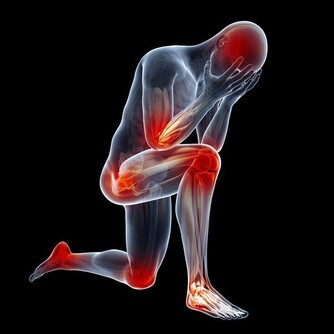

2、在勞累或運動後,出現肩膀疼痛、後背疼痛、牙齒疼痛、喉嚨發緊等症狀,

且這些症狀會隨著運動的增多而加劇。